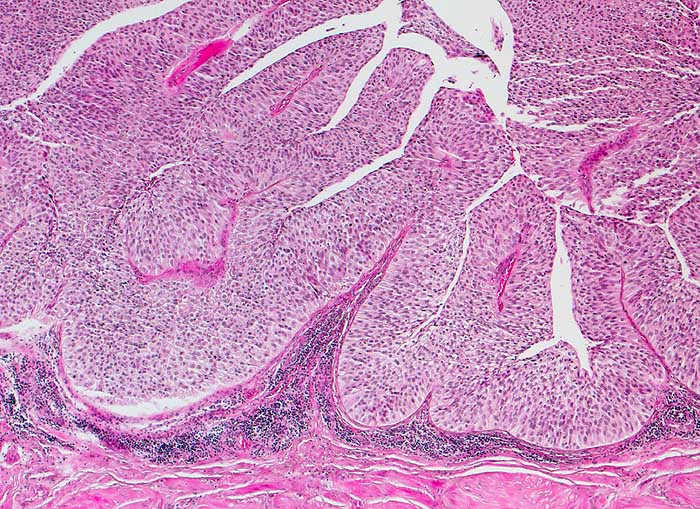

n/ Papilläres Urothelkarzinom pTa, G1 + G2

Papilläres Urothelkarzinom pTa, G1 + G2

Bei den meisten papillären Urotheltumoren finden sich kleine Büschel von kubischen oder zylindrischen Urothelien. Die Kerne sind leicht vergrössert, oft spindelig und hyperchromatisch. Papilläre Karzinome mit leichter Epitheldysplasie sind aufgrund der sehr geringen Zellatypien in bis zu 50% der Fälle zytologisch nicht diagnostizierbar. Bei mässiger Epitheldysplasie sind die Urothelien polymorpher und hyperchromatischer.

Unten werden Beispiele von einem hoch differenzierten und drei mässig differenzierten papillären Karzinomen gezeigt.